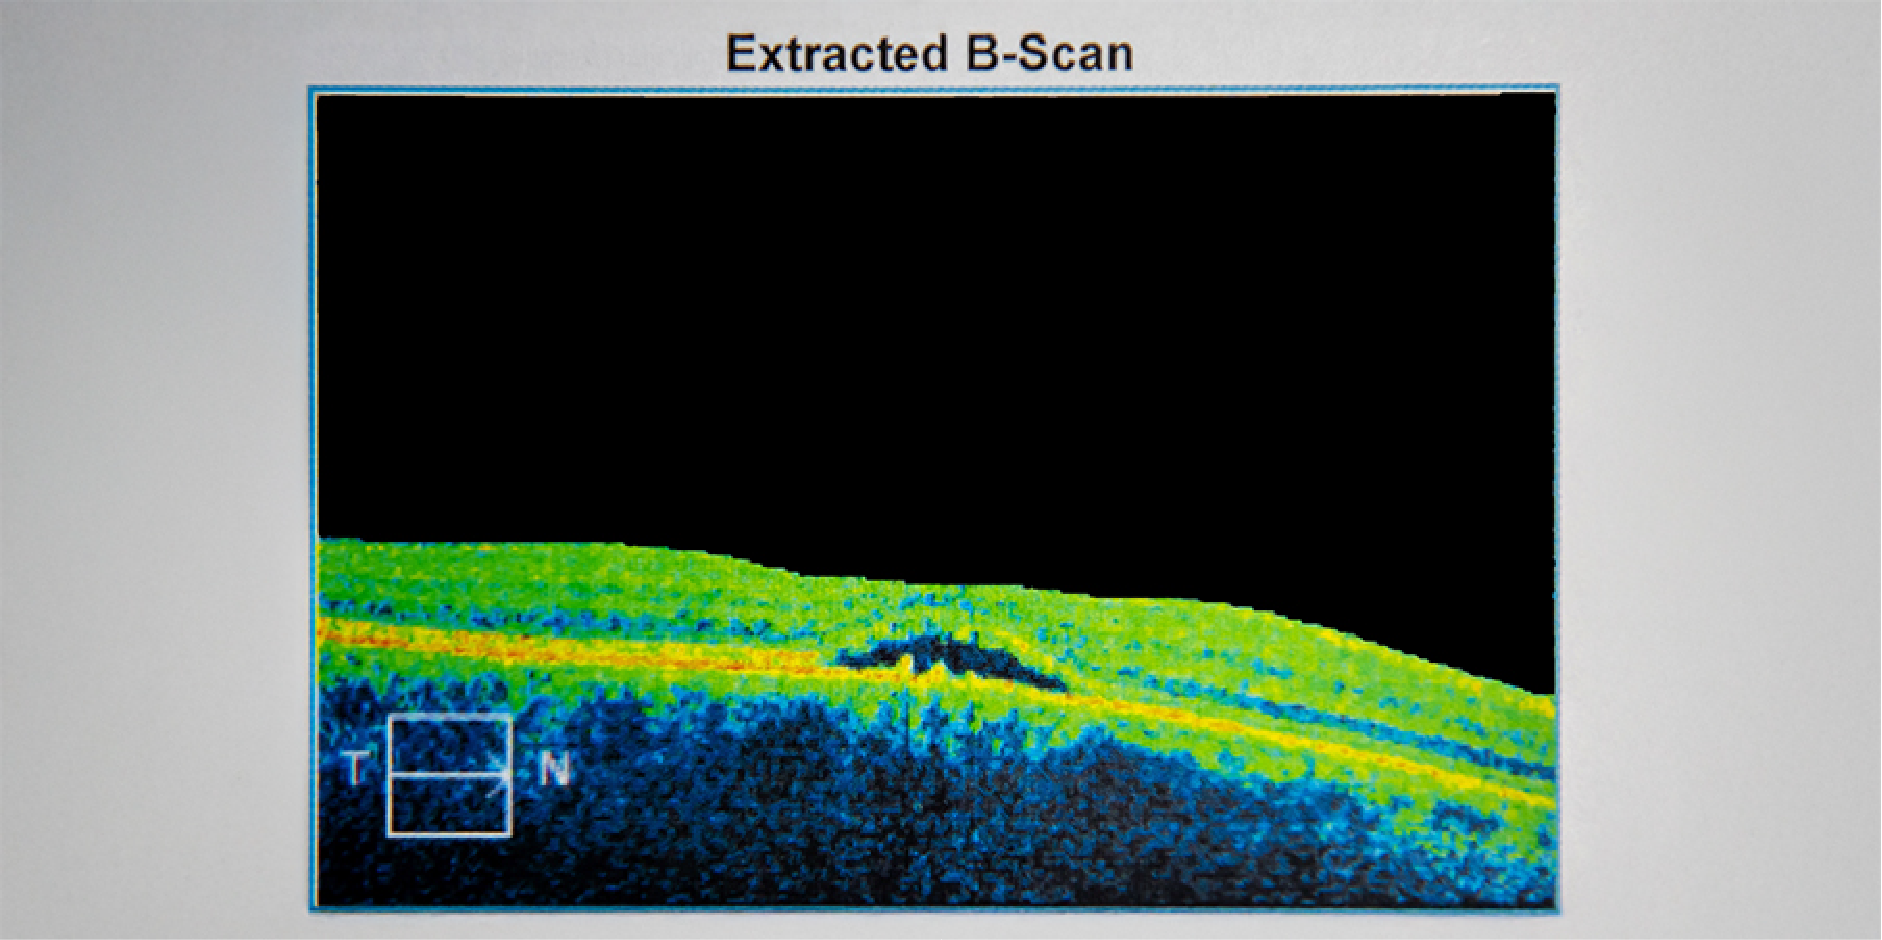

Optic Coherence

Tomography (OCT)

tomography provides a cross-sectional view of the retina that can identify soft

drusen, RPE detachments, subretinal and intraretinal fluid, CNV, cystoid

macular edema, as well as the integrity of the photoreceptor and RPE layers. It

helps to distinguish the causes of visual loss that are not directly associated

with AMD (eg subtle epiretinal membrane or vitreomacular traction). It also

allows the evaluation of the RPE and photoreceptor layer to identify the

anatomic causes of metamorphopsia and visual acuity loss. It helps determine

the presence of subretinal fluid and degree of retinal thickening which are the

earliest manifestations of neovascularization. Lastly, it accurately follows

the structural changes that can be used in evaluating the retina and RPE

response to therapy.